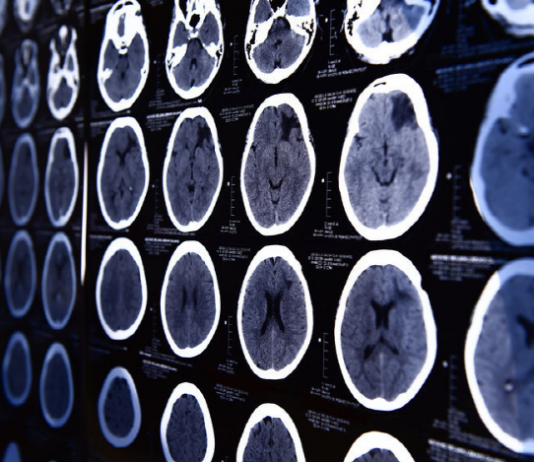

사람의 뇌는 금주 후 7개월 만에 알코올로 인한 손상에서 회복할 수 있는 것으로 밝혀졌다.우리 뇌는 맥주 한 캔의 절반 정도만 마셔도 뇌가 위축되는 등 알코올은 뇌에 심각한 손상을 입히는 것으로 알려져 있다. 과음한 적이 있는 사람의 뇌를 스캔한 결과, 6개월 이상 금주하면 뇌를 크게 회복시킬 수 있다는 연구 결과가...